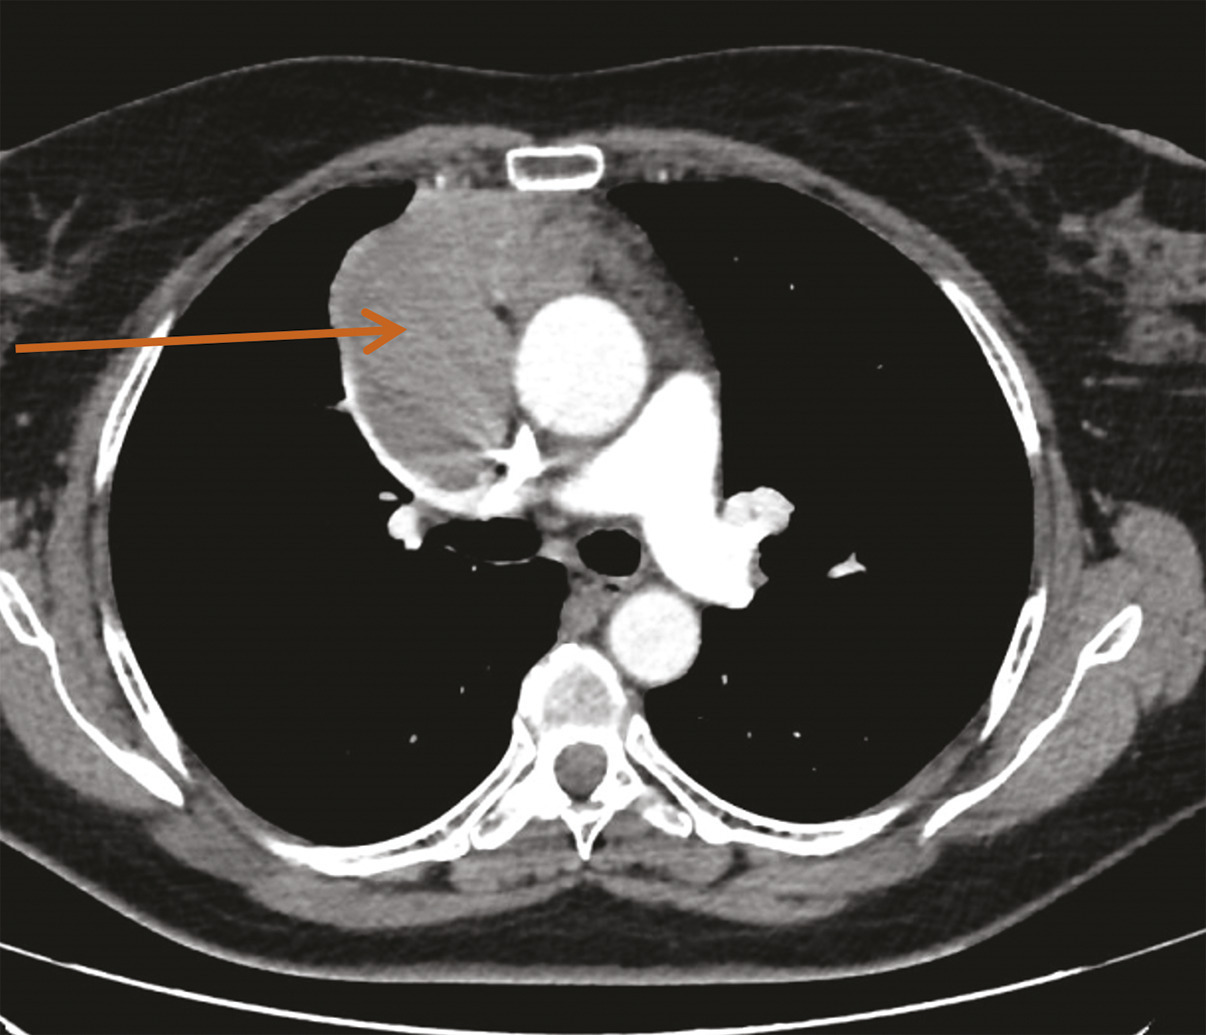

Chez cette patiente, on décide de prescrire une chimiothérapie néoadjuvante par CAP (cisplatine 50 mg/m², adriamycine 50 mg/m², cyclophosphamide 500 mg/m²). Trois cycles sont reçus, avec une bonne tolérance. L’évaluation RECIST 1.1 décrit une stabilité globale tumorale avec cependant une diminution de 10 % en taille de la lésion. La tumeur est résécable.

Une évaluation neurologique est nécessaire afin d’encadrer le geste chirurgical. Mme C. reçoit ainsi en préopératoire une injection d’immunoglobulines par voie intraveineuse afin d’éviter une exacerbation des symptômes myasthéniques en périopératoire. La chirurgie consiste en une sternotomie médiane, avec exérèse de la tumeur médiastinale et bilobectomie supérieure. Face à l’envahissement péricardique et pulmonaire adjacent, la tumeur est classée stade III (dans la classification de Masaoka-Koga), et stade T3N0M0, soit IIIA (dans la classification TNM). Les marges de résection sont saines (R0).6, 7